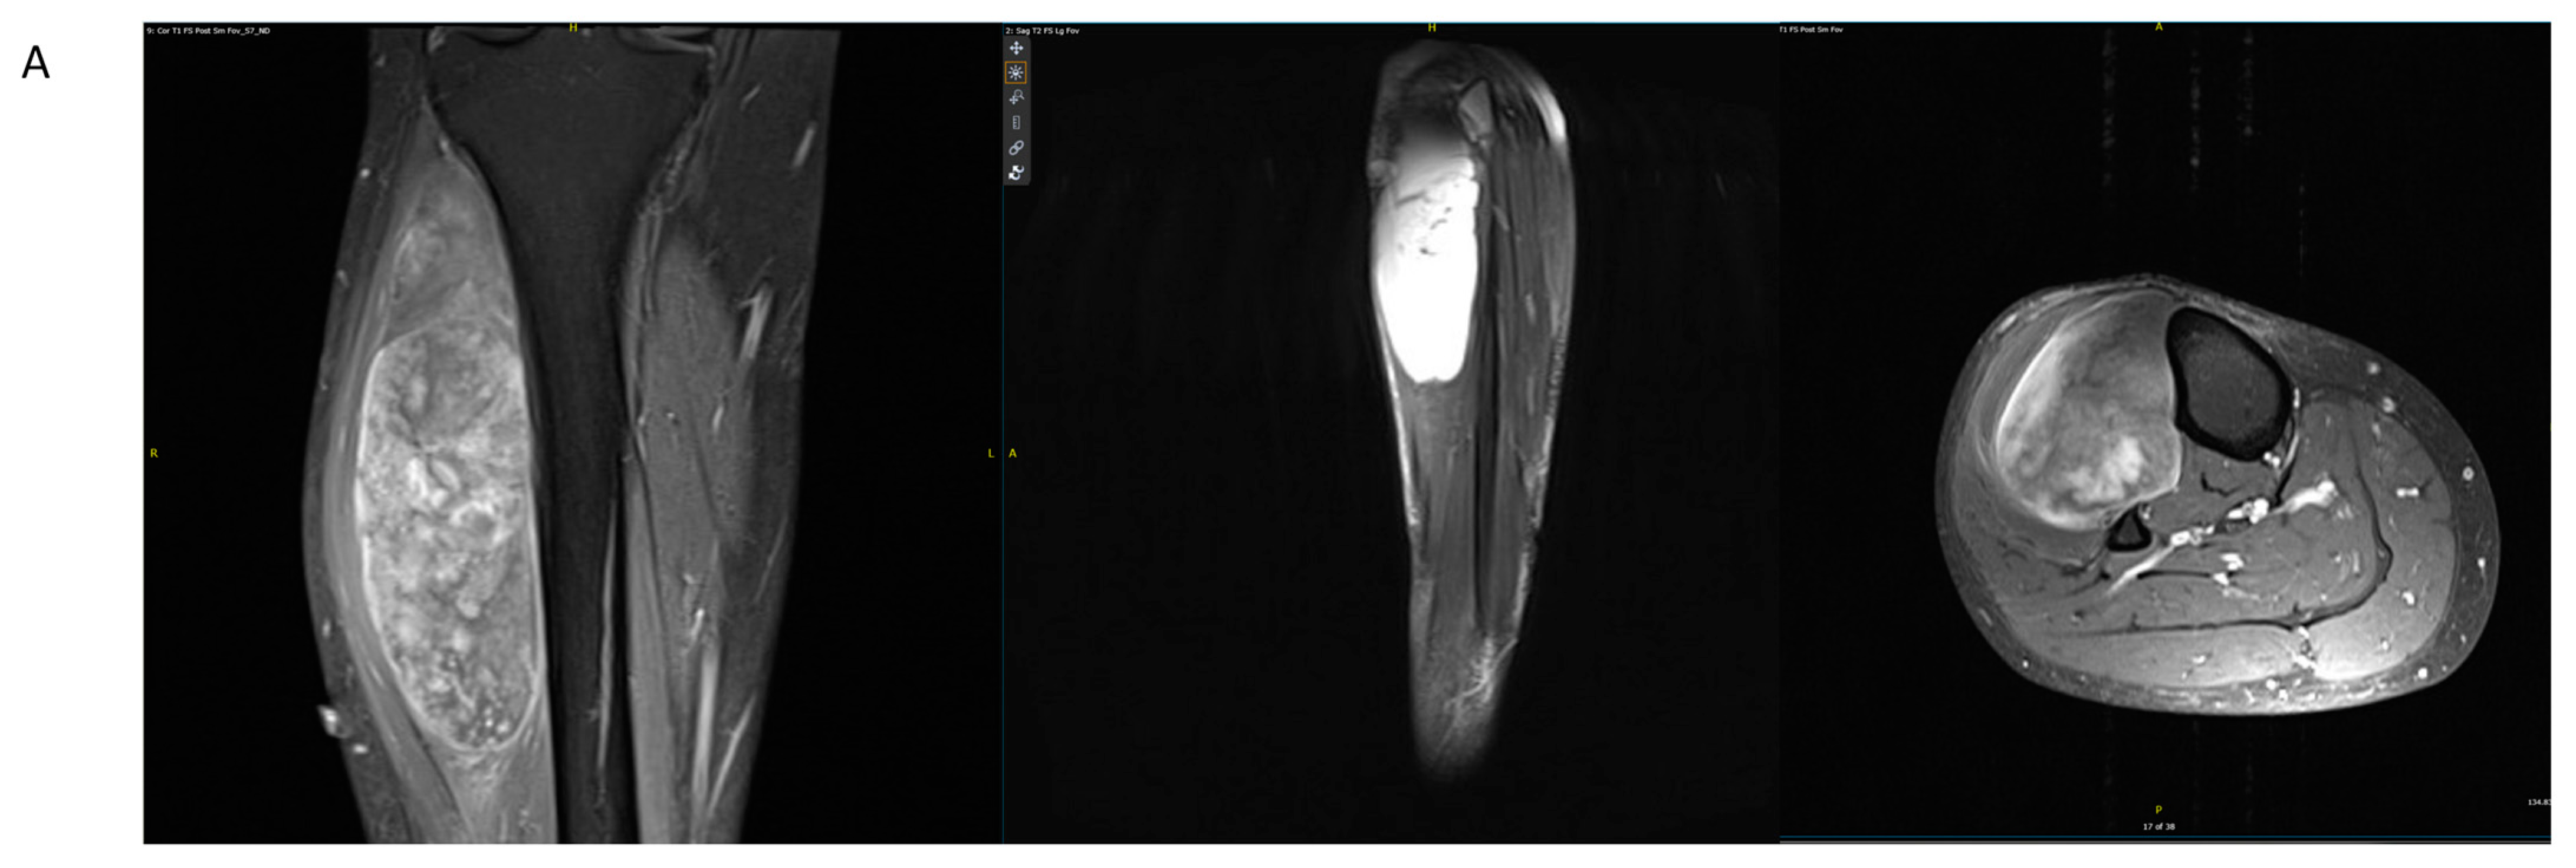

4.1. Case Example 1–Prophylactic Fixation via Intramedullary Nailing following Resection of Cortical Margin for Myxoid Liposarcoma Resection